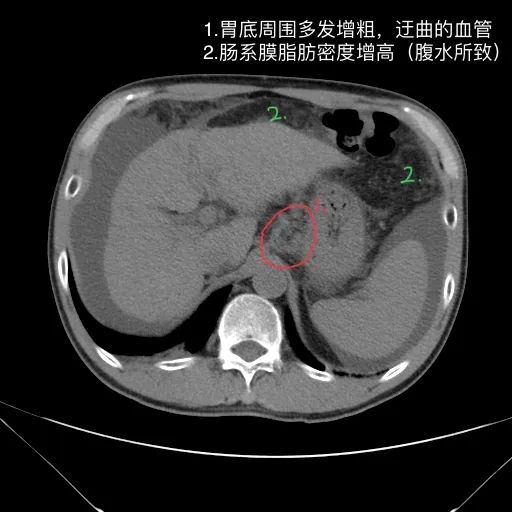

肝脏缩小,包膜凹凸不平,肝裂增宽,各叶比例失衡,肝实质密度不均,肝S4小片低密度影,约cm;胆囊不大,其内未见异常密度影,胆道系统未见扩张;胰腺、脾脏形态、密度、大小未见异常;双肾上腺及双肾形态、密度、大小未见异常,双输尿管未见扩张,膀胱充盈良好,壁光滑,其内未见异常密度影;前列腺未见异常;胃肠道未见充盈,壁未见明确增厚,食管胃底多发迂曲、增粗血管,腹部及腹膜后未见肿大淋巴结;腹水。

1.肝硬化失代偿表现(腹水,食管胃底静脉曲张)。